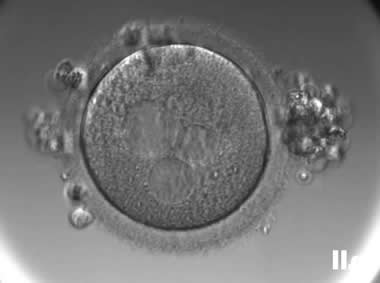

3. 成熟卵母细胞(MII)及其COCs(正常COCs)

卵细胞呈现规则的圆形且颜色较浅,放射冠完全分散,颗粒细胞团较大,排列稀疏。成熟卵母细胞一般在取卵后体外培养2-6小时再行授精。

|  |

| 0小时COCs的MII卵(4x) | 0小时COCs的MII卵(10x) |

|  |

| 2小时COCs的MII卵(10x) | 4小时去颗粒细胞后的MII卵(10x) |